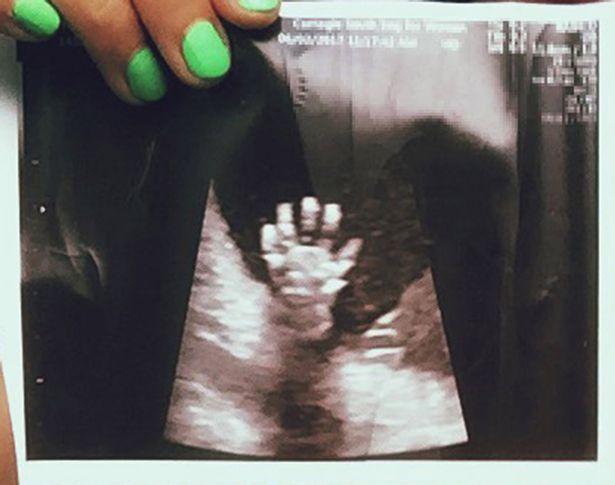

Libby cầm bức ảnh siêu âm lúc mang thai 20 tuần

Trong lần siêu âm ở tuần thứ 20, cặp đôi vô cùng ngạc nhiên khi nhìn thấy con gái giơ cả bàn tay lên, xòe ra 5 ngón. Cặp vợ chồng đăng bức ảnh này lên mạng xã hội và nó lan truyền nhanh chóng, theo Mirror.

Bé gái giơ cả bàn tay lên, xòe ra 5 ngón